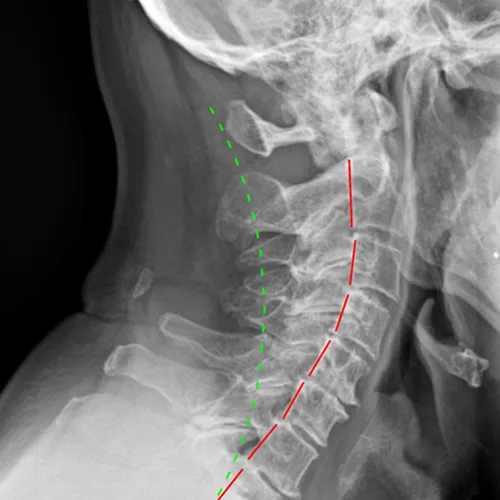

Osteoarthritis can affect your spine, hips, knees, shoulders, hands or any joint in your body. While traditional treatments often focus solely on pain medication, our approach addresses the mechanical aspects of the condition – how your joints move, align, and function. When joints aren’t moving properly, it can accelerate wear and tear, leading to increased pain and stiffness. X-rays are commonly used to identify the severity of the osteoarthritis and joint misalignments.